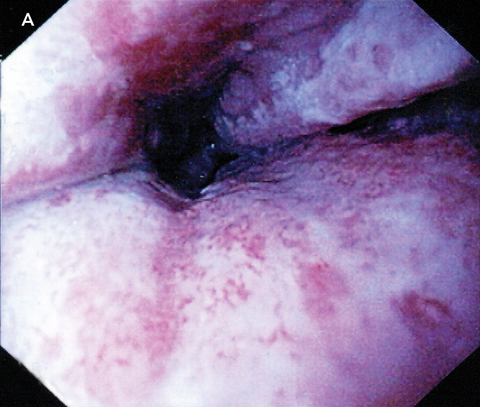

We describe a previously unreported association between hyoscine hydrobromide and severe oesophagitis, with ulceration visible almost to the submucosa in the distal oesophagus. The condition resolved with cessation of tablets and 2 months’ treatment with a proton-pump inhibitor.

Medication-induced oesophagitis may result from either local or systemic effects of a drug. Direct mucosal injury occurs after prolonged exposure of the oesophageal mucosa to the caustic contents of the medication.2 Examples of medications known to cause this type of injury include tetracycline, aspirin and non-steroidal anti-inflammatory drugs, as well as alendronate, potassium chloride, and iron compounds. Endoscopy often reveals a discrete ulcer with relatively normal surrounding mucosa.3 Risk factors for retention of pills in the oesophagus include a lack of adequate liquid bolus, lying down after swallowing, and older age.2,4

Although we could find no reports of hyoscine hydrobromide having a direct toxic effect on the oesophagus, the related compound hyoscine butylbromide has been shown to significantly increase the number of reflux episodes compared with placebo,5 in contrast with atropine, another anticholinergic, which has been shown to reduce reflux episodes.6 If hyoscine hydrobromide acts similarly to hyoscine butylbromide, it would be reasonable to hypothesise that the oesophagitis in our patient may be secondary to prolonged acid exposure. As the tablets were consumed without water, it is also possible that local mucosal injury may have occurred due to retention of tablets in the lower oesophagus, with subsequent pressure necrosis or caustic injury. Further studies would be required to elucidate the precise mechanism of injury.